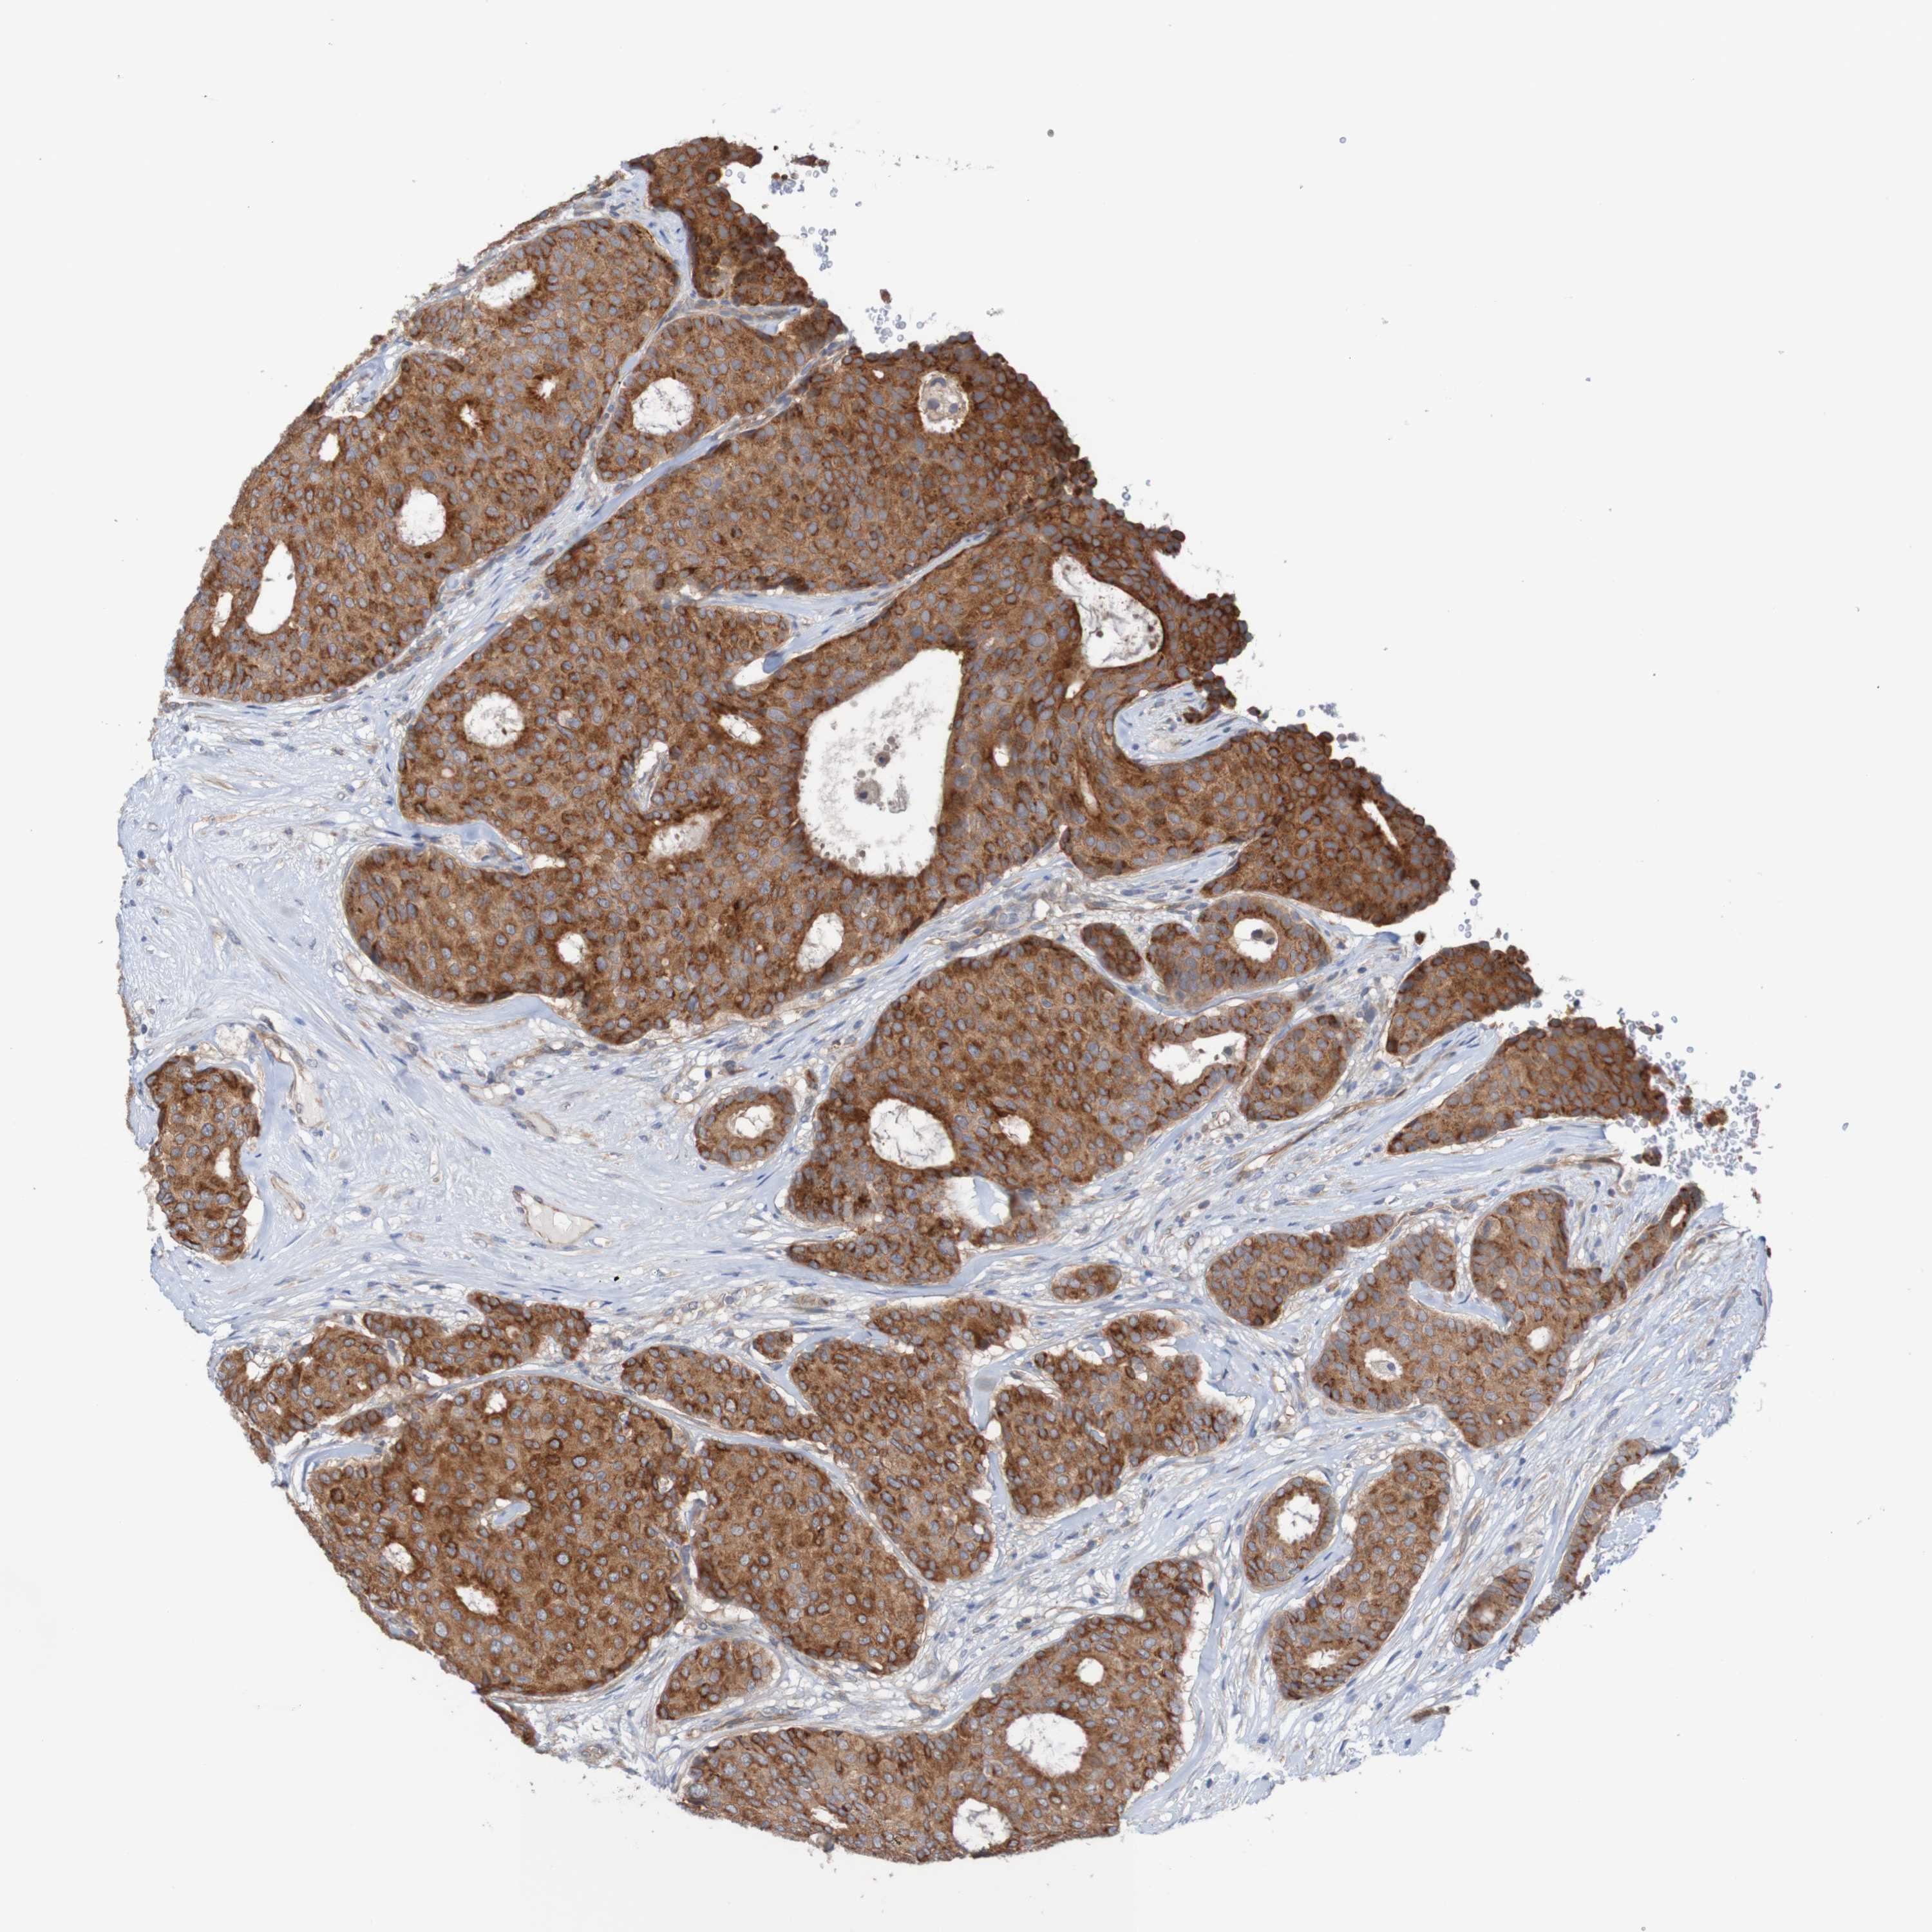

CANCER BREAST CANCER Show tissue menu

BRCA TCGA BRCA VALIDATION PROTEIN EXPRESSION